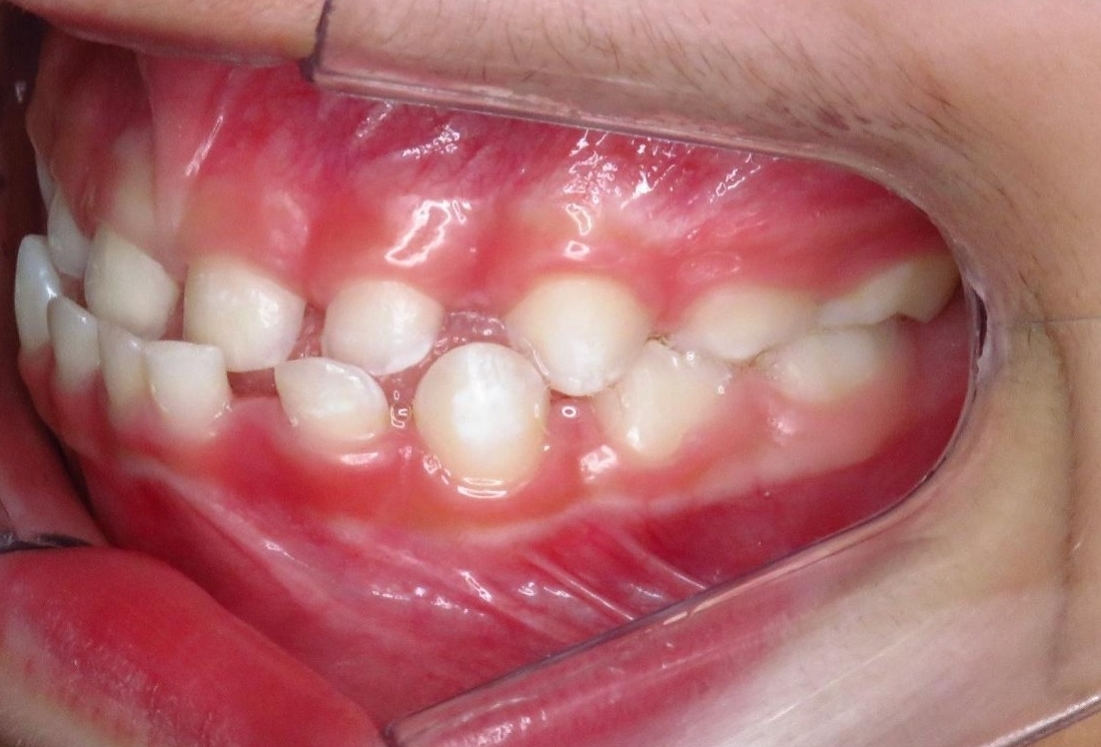

R.P.B.

ORTODONTIA MIOFUNCIONAL